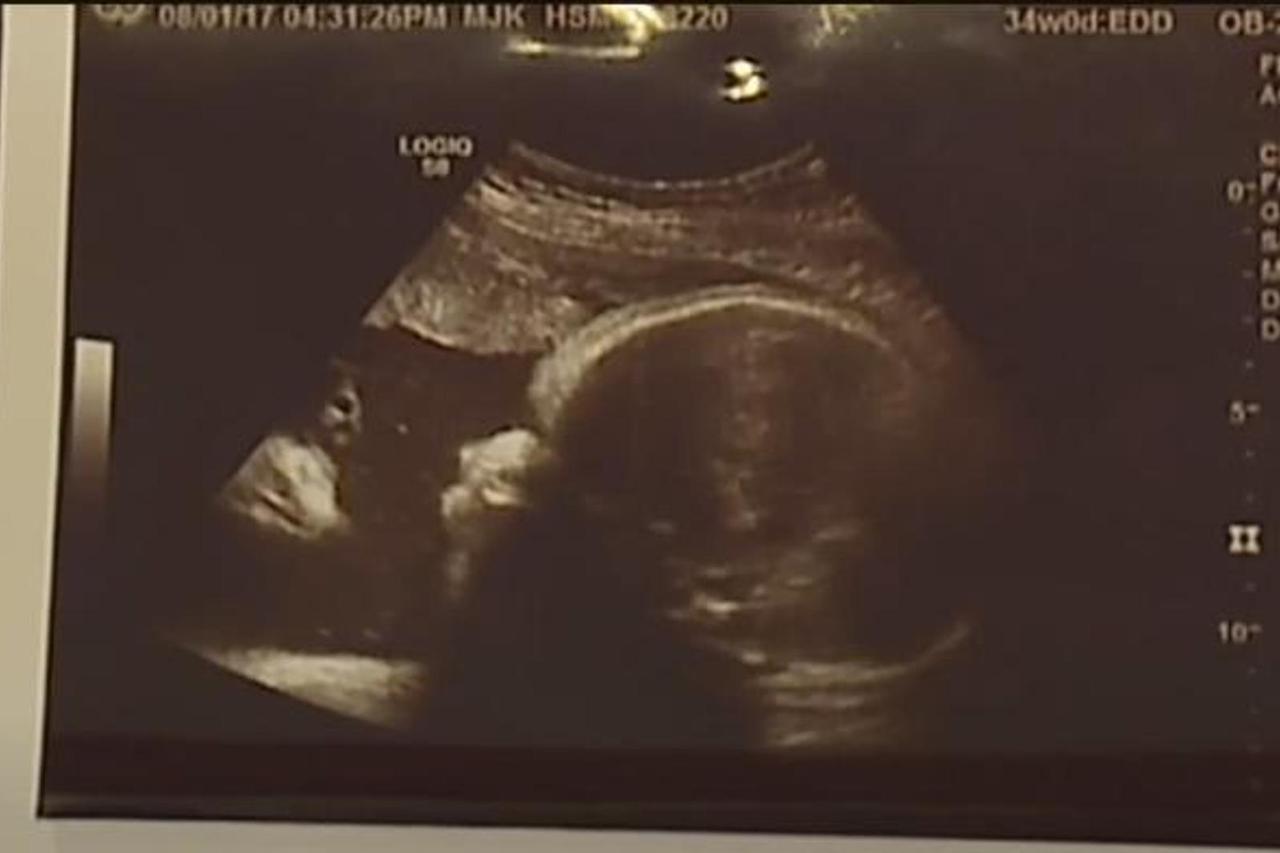

Video sadržaj SLIKA ULTRAZVUKA Roditelji ostali u čudu kada su vidjeli što je kraj djetetove glave: To je znak! Kraj glave djeteta u kutu fotografije nalazi se još jedno lice, a roditelji tvrde kako je riječ o Isusu